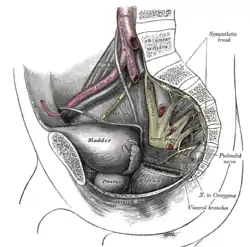

Nerves

The arteries of the pelvis. Dissection of side wall of pelvis showing sacral and pudendal plexuses.

Dissection of side wall of pelvis showing sacral and pudendal plexuses. Sacral plexus of the right side.

Sacral plexus of the right side. Male pelvic cavity

Male pelvic cavity Female pelvic cavity